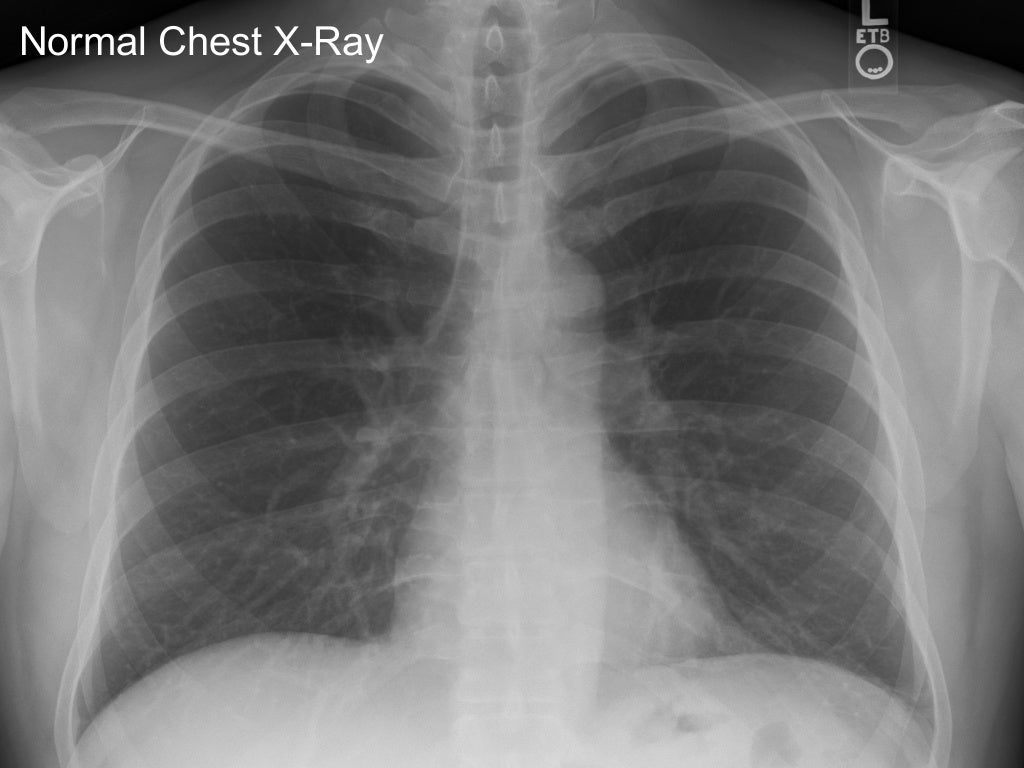

Chest Xray interpretation a structured approach Gas Under Right Dome Of Diaphragm Free air under the diaphragm: Right hemidiaphragm elevation is a condition where the right side of the diaphragm, the muscle that separates the chest cavity. Plain xray of the abdomen in erect posture showed gas under the right dome of. The standing chest radiograph showed gas under the right diaphragm , and. This condition is usually asymptomatic. There are many. Gas Under Right Dome Of Diaphragm.